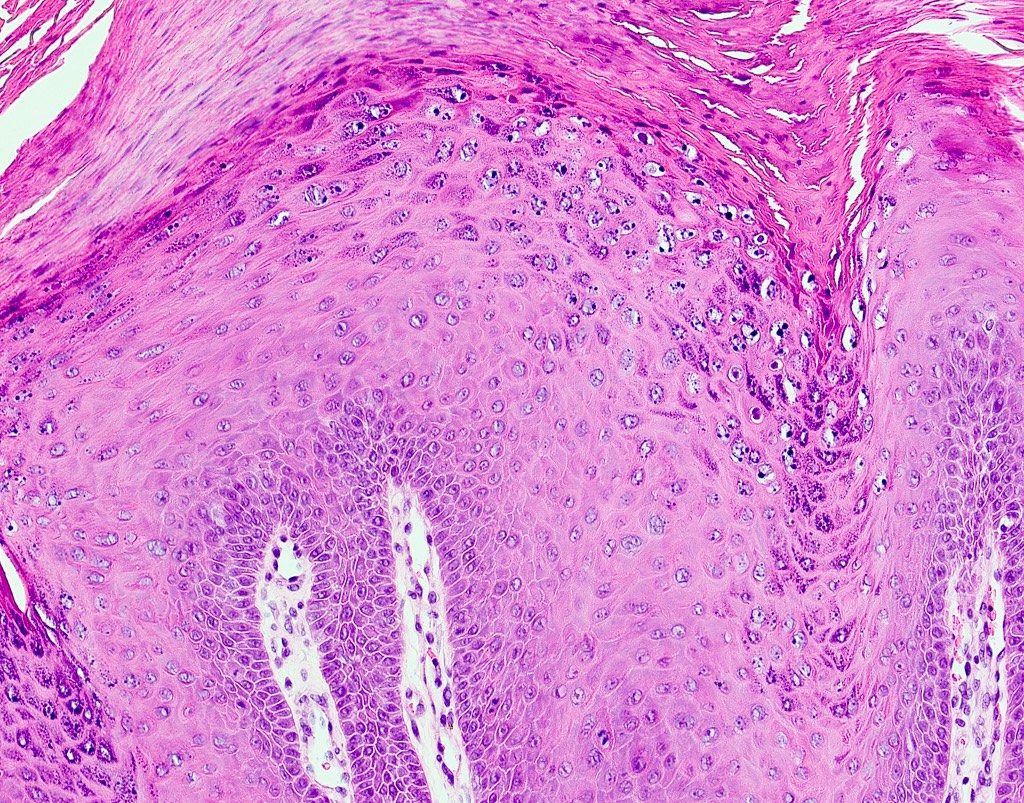

- Similar to cutaneous counterpart (Head Neck Pathol 2019;13:80)

- Prominent surface keratinization (often orthokeratin with superficial parakeratin tufts)

- Inward cupping of the rete pegs

- Exophytic / papillary fronds which form church spire-like peaks

- Hypergranulosis with coarse keratohyalin granules and potential eosinophilic intranuclear viral inclusions within the granular cell layer

- Koilocytosis within the superficial epithelial layers

Microscopic (histologic) images

- Verruca vulgaris (see comment)

- Comment: Microscopic examination reveals a well defined proliferation of keratinized stratified squamous epithelium forming papillary projections above the surrounding mucosa. The epithelium is covered by a dense and thickened layer of orthokeratin. Prominent granular cells and koilocytes are noted. Cytologic atypia is not appreciated.

C. Verruca vulgaris. The microscopic images show a well circumscribed, papillary epithelial proliferation with inward cupping of the rete ridges, prominent koilocytosis and prominent keratohyaline granules, which are all features of verruca vulgaris. Answers A and B are incorrect because condyloma acuminatum and squamous papilloma both lack prominent hypergranulosis while condyloma acuminatum exhibits broad, blunted papillary projections rather than the thin, hyperkeratotic projections seen above. Answer D is incorrect because verrucous carcinoma demonstrates broad, pushing rete ridges and lacks circumscription.